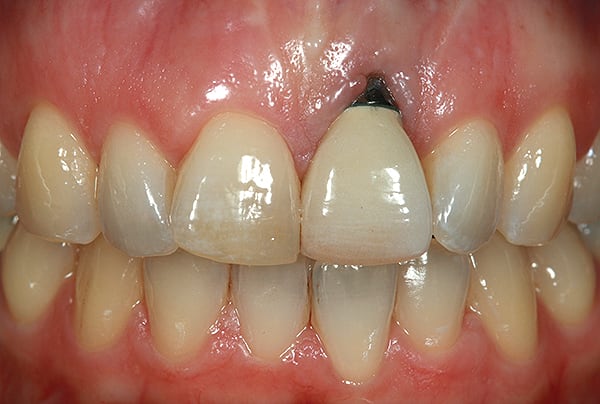

Before a clinician can decide on treatment, a diagnosis must be made whether the implant is healthy or not, meaning normal bone levels around the implant. Another decision of concern was whether to retain the dental implant. It was determined that the implant was healthy, however the recession defect was due to an overcontoured custom abutment secondary to excessive facial implant angulation (Figure 3). The tendency for most surgeons when presented with such a recession defect is to think of a “root” coverage type surgical procedure. Patients with a thin or intermediate phenotype may not respond well to such a technique. It was also mentioned previously that an exposed implant abutment is absent of blood supply and may be contaminated with endotoxins that would constrain the predictability of healing with a coronal positioned connective tissue flap. One of the tactics to predictably ensure primary flap closure of the defect is to “decoronate” or bury the implant12,13 by removing the existing implant abutment and placing a surgical cover screw (Figure 4). Consequently, the soft tissues will heal and cover the head of the implant—“nature’s connective tissue graft” or spontaneous in-situ gingival augmentation. A resin-bonded–retained bridge was used as a provisional transitional restoration (Figure 5 and Figure 6). After a 2-week period, closure of the tissue was evident but de-epithelialization was required to ensure completion (Figure 7). Three-months post-ridge healing, sounding to the implant head with a periodontal probe revealed 5 mm of coronal soft tissue thickness (Figure 8). It was then decided that a secondary ridge augmentation procedure was not necessary, only second-stage implant uncovering surgery was needed with a crestal incision biased toward the palate. The shape of the patient’s pre-existing abutment was modified creating a flat facial contour, disinfected, and replaced as a provisional abutment (Figure 9). The original crown was also used as a temporary following an acrylic reline (Figure 10). After 1-month post-implant exposure, a new acrylic provisional restoration was fabricated and used to re-shape and sculpt the soft tissues to match those of the contralateral natural tooth14 (Figure 11). The flat contour concept of the abutment restoration is followed throughout the definitive abutment (Figure 12) and crown restoration (Figure 13 and Figure 14). Figures 15 and 16 show the intraoral and smile view of this patient, respectively, receiving remedial treatment at 5-years post-surgical treatment.